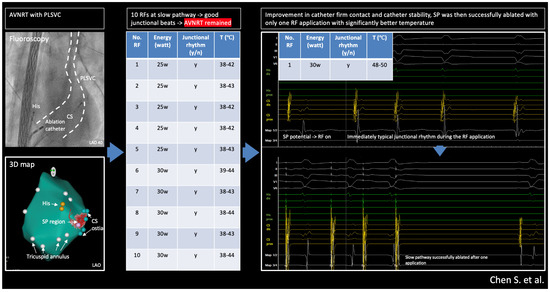

2.3. Ablation Strategy

2.4. Outcome